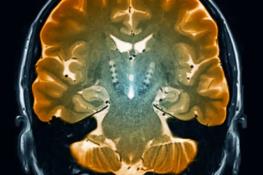

شناسایی سلول‌های مغزی مرتبط با بیماری پارکینسون

زیرگروهی از سلول‌های مغزی که در بیماری پارکینسون از بین می‌روند با استفاده از روشی جدید که نشان می‌دهد کدام ژن‌ها در هر سلول‌ فعال هستند، کشف شده است.